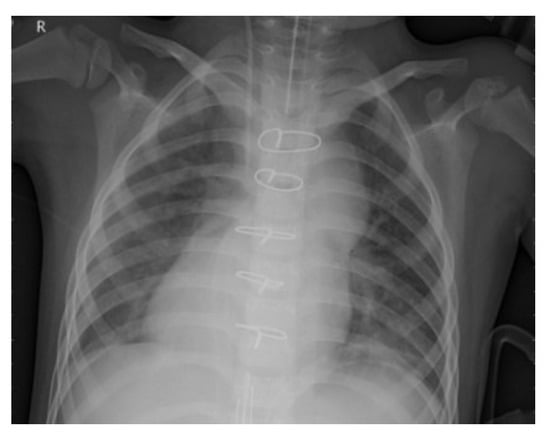

To improve the authenticity of the research, this paper selected a large number of athletes from professional sports colleges. X-ray images of the above athletes’ lungs were collected. There were 2806 men and 2806 women, totaling 5612, accounting for 30% of the unit athletes in 2020. The ages were between 18 and 25 years old. The shortest training period was only 1 year and the longest training period was 5 years. Figure 6 and Figure 7 are the medical images of the part collected.

Figure 6. Lung image without pneumonia.

Entropy 24 01434 g006